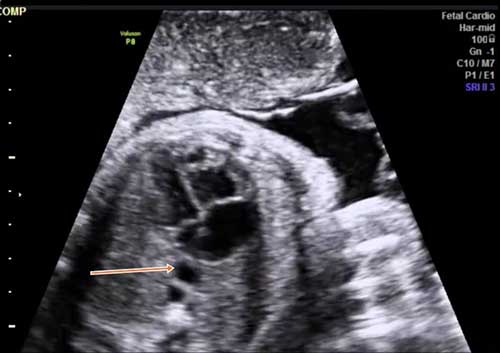

This image quiz focuses on the kidneys. Can you identify the abnormality seen in these ultrasound images of the fetal abdomen?

Challenge your diagnostic skills: What's going on with the kidneys in this fetus?